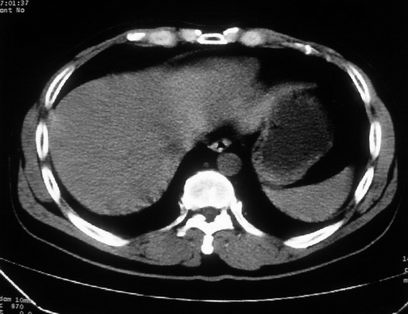

男,体查发现右肝低密度,右肾高密度结节影。高密度ct值92hu,囊肿?

肝右叶囊肿或血管瘤?右肾高密度囊肿。建议增强。

肝右叶囊肿,右肾高密度囊肿。建议增强。

肝右叶圆形低密度灶,考虑囊肿或血管瘤,建议ct增强检查;右肾包膜下高密度圆形灶,考虑:囊肿并出血